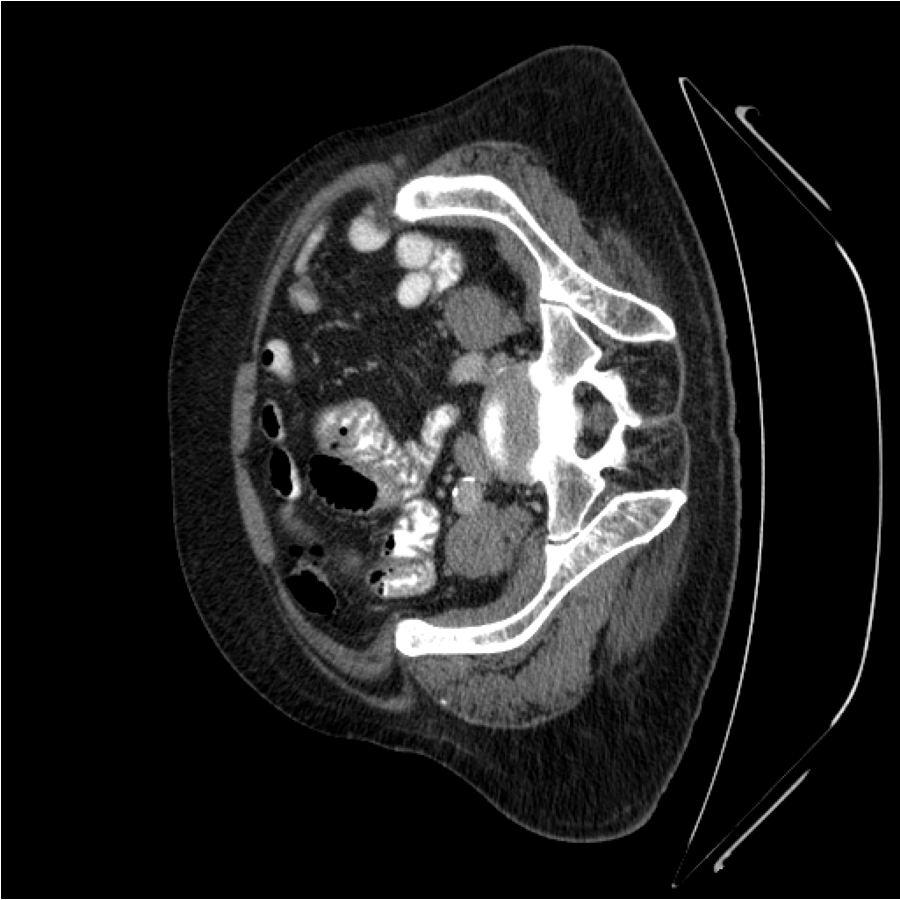

Figure 4: (a)(b)(f)(g) Training images; (c)(d)(e)(h)(i)(j) Generated augmented images with outlined superpixel grids in green color. The numbers of superpixels, l1l_{1} and l2l_{2} corresponding to either training image, are fixed here for visualization.

In general, increasing the number of superpixel, ll, leads to a finer granularity that provides less semantic information but more contour information. Conversely, decreasing in the superpixel number results in a coarser granularity that provides less contour information but more semantic information. As can be seen in Figure 4, the superpixels in Figure 4(c) and Figure 4(h) have a higher level of semantic information but lower capacity of contour information when the superpixel number, denoted by ll, is relatively small. In Figures 4(e) and 4(j), the number of superpixels, ll, is relatively large. Consequently, although the synthetic superpixel maps have detailed boundaries, they lack semantics. For images with a large amount of fine-grained content or granularity, it is recommended to use a relatively large number of superpixels, where each superpixel is relatively small. Conversely, a small number of superpixels can also be used, with each superpixel being relatively large. In our method, the number of superpixels ll for each image is randomly determined according to a uniform distribution lU(lmin,lmax)l\sim U(l_{min},l_{max}) instead of setting it as constant. This is easier to tune and can increase the diversity of the augmentation space. It can also improve the robustness of our method. The quantitative analysis is shown in Table 8.